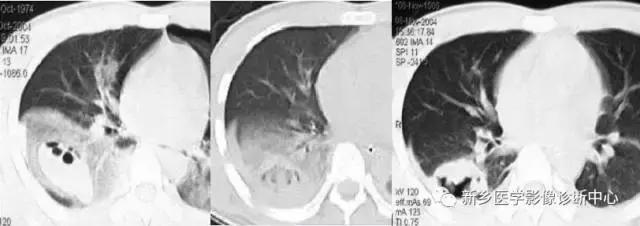

包虫囊肿

好发于肺中下野,继发感染时有发热,咳嗽胸痛,常见于牧区。圆形密度增高影,边缘清楚,内为水样密度,“水上浮莲征”为特征表现。

左图:右肺上叶小的破裂包虫囊肿,塌陷的棘球蚴包膜“水上浮莲征”

右图:充满整个右半胸腔巨大包虫囊肿。